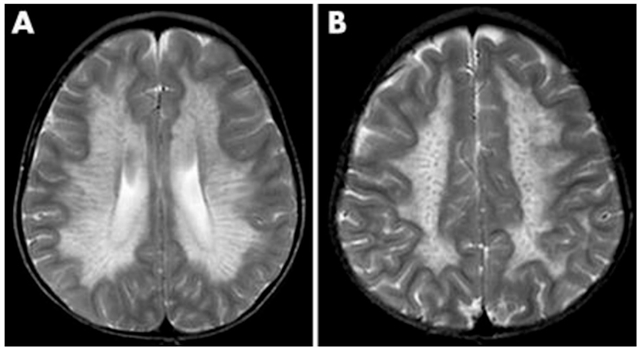

• MRI 特征:早期脑室周围白质对称性脱髓鞘,进展后出现特征性 **“虎纹征” 与 “豹纹征”**,胼胝体压部受累为典型标志。

异染性脑白质营养不良的 MRI 表现(A)呈低信号放射状条纹,类似虎皮外观(虎纹征)。(B)呈低信号点状改变,类似豹皮外观(豹纹征)。